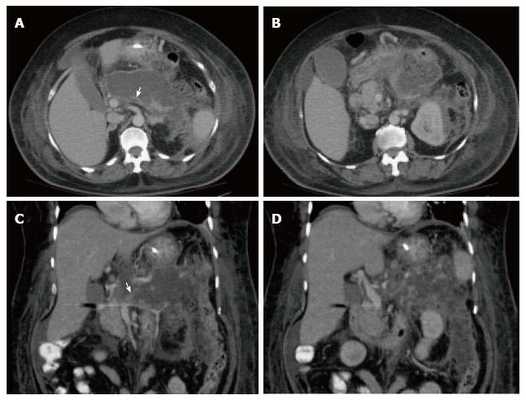

(Левый) На поперечном срединном УЗ срезе в ложе поджелудочной железы определяется гетерогенное скопление, содержащее нежидкостные фрагменты, что указывает на развитие некроза поджелудочной железы и перипанкреатических тканей.

(Правый) У этого же пациента при КТ с контрастным усилением на поперечной томограмме наблюдается полное отсутствие контрастирования тела и хвоста поджелудочной железы, что характерно для панкреонекроза. Также определяется пери панкреатическое скопление жидкости, содержащее нежидкостные фрагменты, это указывает на острый некроз перипанкреатических тканей и формирование очага острого некроза.

(Левый) На поперечном УЗ срезе определяется увеличенная гипоэхогенная поджелудочная железа, что характерно для острого панкреатита. Спереди от железы определяется скопление жидкости. Наличие и распространенность некроза оценить трудно.

(Правый) У того же пациента при КТ с контрастным усилением на поперечной томограмме большая часть поджелудочной железы не контрастируется, что указывает на развитие некроза; в хвосте железы определяется остаточная жизнеспособная ткань. Граница между передним краем поджелудочной железы и очагом острого некроза различима с трудом.